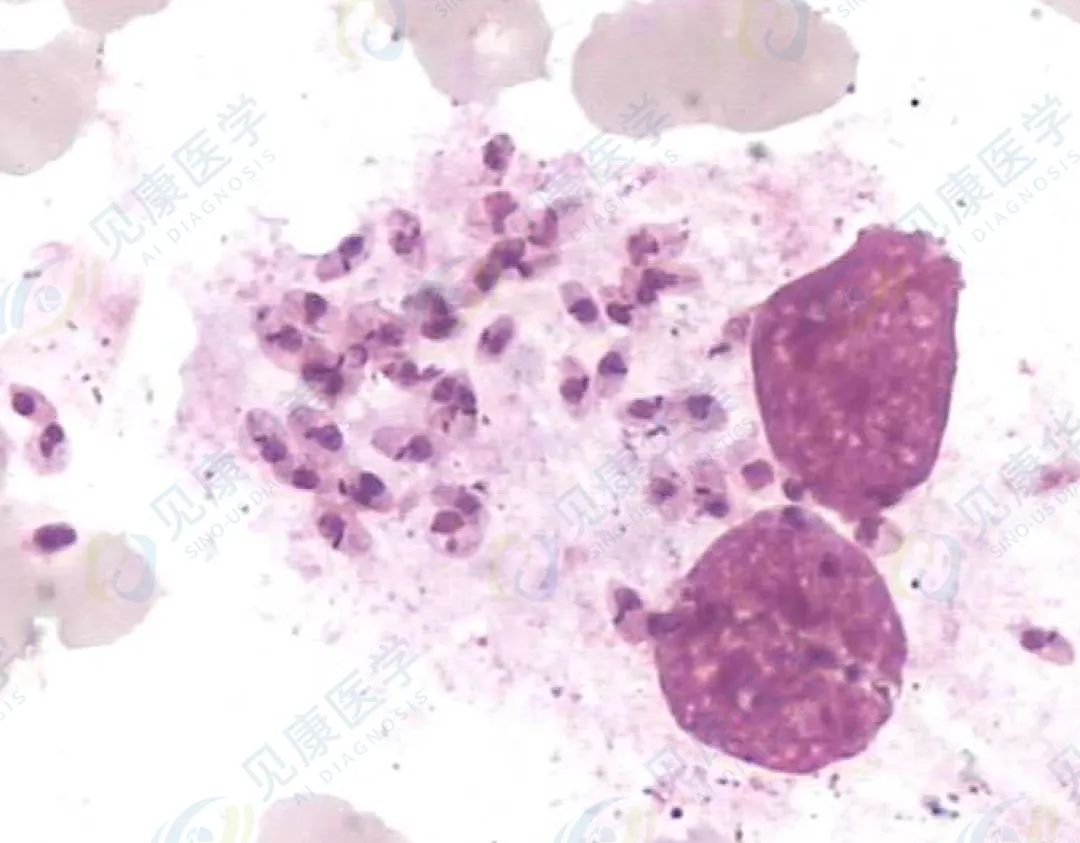

黑热病(利-杜小体)

(示意图)

黑热病的病原体,与血小板大小相似,胞质淡蓝色,胞核紫红色,核旁有一紫红色、杆状的动基体,黑热病患者骨髓中可见利杜小体,外周血少见。